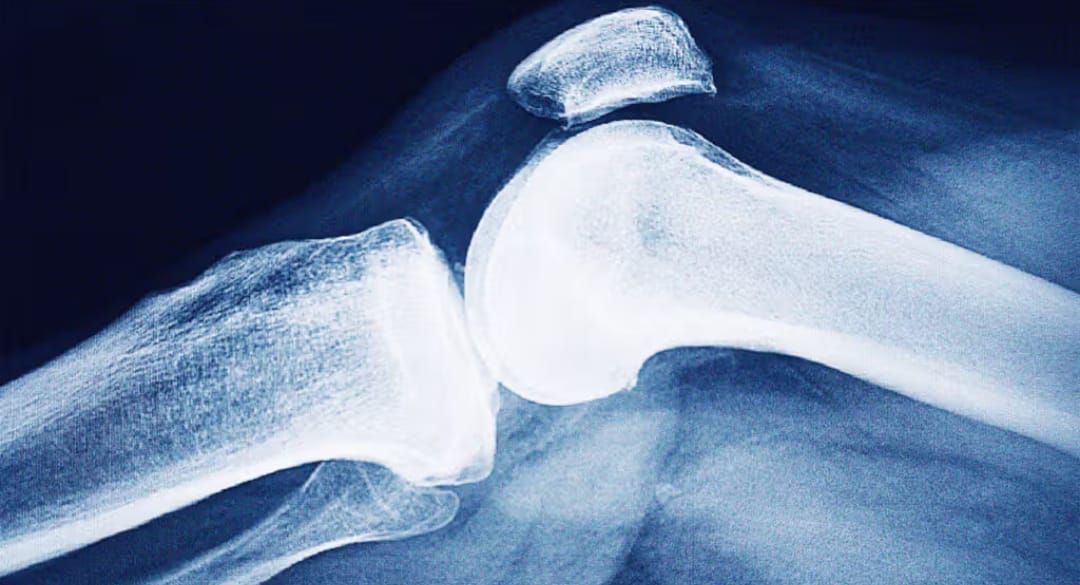

L’ostéoporose fragilise l’os et expose aux fractures dites «de fragilité» (chute de sa hauteur, geste banal). Longtemps asymptomatique, elle se révèle souvent par une première fracture – vertèbre, poignet, hanche – qui en appelle d’autres si rien n’est fait. Chaque octobre, la Fondation internationale de l’ostéoporose (IOF) rappelle l’ampleur du fardeau et la nécessité d’un parcours systématique après fracture.

Réduction de la masse et de la qualité de l’os, donc de sa solidité, avec risque fracturaire accru. Le diagnostic s’appuie sur la densitométrie (DXA): un T-score ≤ −2,5 au rachis ou à la hanche confirme l’ostéoporose, même sans fracture. Le «capital osseux» se constitue jusqu’à l’âge adulte, se maintient jusqu’à ~40 ans, puis décroît d’environ 1–2% par an; après la ménopause, la perte s’accélère sous l’effet du déficit œstrogénique.